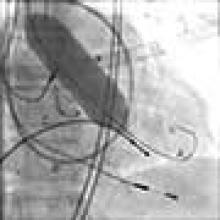

The Sapien valve is a balloon expandable platform and it comes in two sizes, 23 mm and 26 mm. The valve is prepared and mounted onto a sheath system for implantation on the back table. The femoral arterial access is serially dilated to accommodate a 22 French (for 23 mm Sapien valve) or a 24 French (for 26 mm Sapien valve) sheath. The balloon mounted valve is then advanced in a retrograde fashion into the aortic valve position using angiographic and echocardiographic guidance (Figure 2). It is important to visualize the position of the valve using at least 2 different angles. For the transfemoral approach, the recommended positioning of the prosthesis is 60%-40%, which is 60% of the prosthesis should be on the ventricular side of the aortic annulus with 40% of the prosthesis on the aortic side of annulus. This is due to the past experience observation that the prosthesis has a tendency to migrate in the aortic direction during deployment. This phenomenon is likely a result of the stored torque in the delivery system when introduced from the femoral artery. For ease of prosthesis arch transit, the delivery platform is equipped with the Retroflex system from Edwards. Of note, the correct orientation of the prosthesis should be confirmed both visually prior to placement into the introducer sheath and angiographically prior to deployment. Next, transvalvular flow is severely depressed by rapid ventricular pacing. The valve is then balloon expanded rapidly and implanted in position. If there is moderate to severe aortic insufficiency from a paravalvular leak after the deployment, a second ballooning with a larger volume is performed under conditions of rapid ventricular pacing.